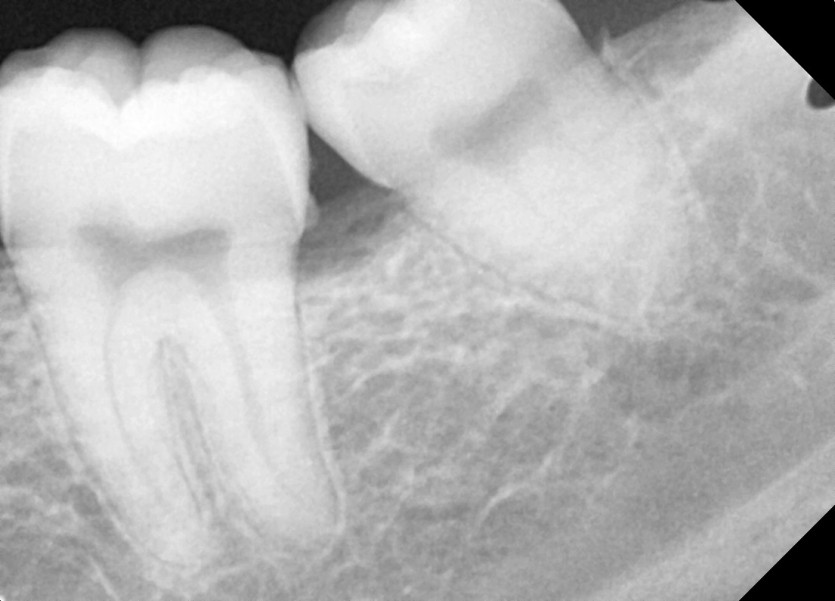

#38 사랑니 발치

구강 외과 전문의가 당일 발치했습니다.